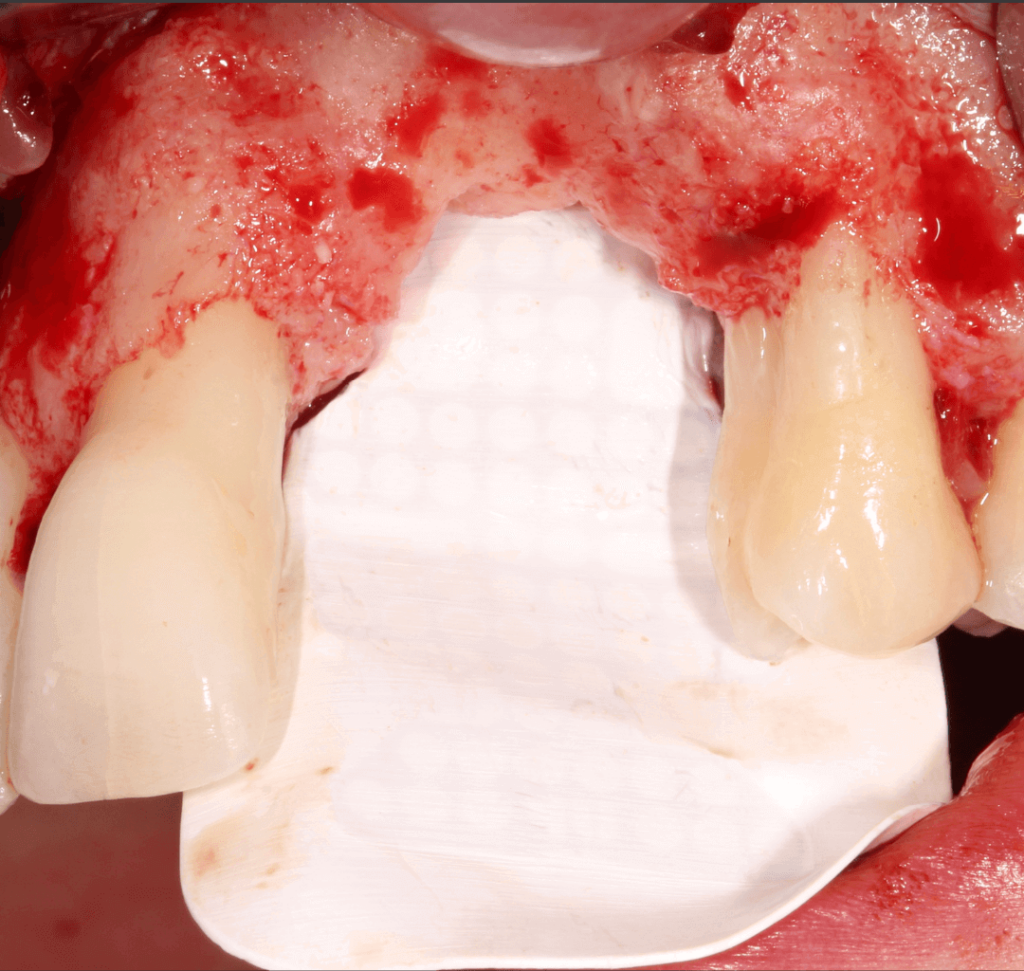

- 3 months later: (which turned out to be 2 years later because the patients was treated and failed elsewhere): 3D guided bone regeneration using 100% autogenous bone and a PTFE, Ti-reinforced NeoGen® membrane which was fixed by Neoss Tacks.

1 NeoGen Ti-Reinforced PTFE Membrane.